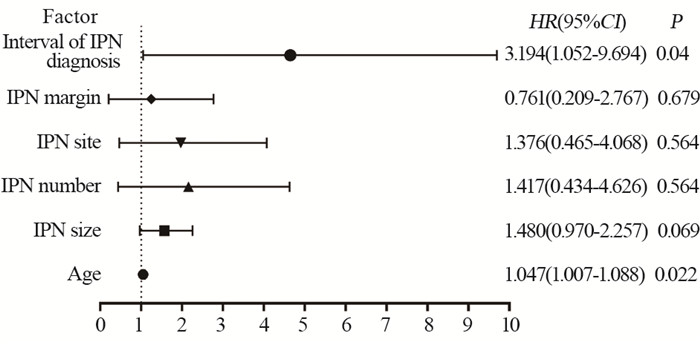

结果IPN平均大小6.453±0.864 mm。IPN直径、形状、密度及结节发现间期可能是恶性转归相关的CT影像特征。年龄(HR=1.047, 95%CI: 1.007~1.088)与结节发现间期(HR=3.194, 95%CI: 1.052~9.694)是影响恶性IPN患者生存期的独立因素。

ResultsThe IPN size of 82 patients was 6.453±0.864 mm. IPN diameter, shape, density, and nodule discovery interval may be CT imaging features related to malignancy tendency. Age (HR=1.047, 95%CI: 1.007-1.088) and interval between each nodule discovery (HR=3.194, 95%CI: 1.052-9.694) are independent factors that affect the survival of patients with malignant IPN.

43例恶性转归的IPN高级别STS患者中,25例死亡、18例存活,平均生存期为28.442±20.041个月。将患者性别及IPN的CT影像学特征对IPN诊断后生存期的影响进行单因素分析。结果显示,IPN位置以及结节发现间期与恶性转归的IPN高级别STS患者的IPN诊断后生存期相关,见表 2、图 1。进一步将表 2中P<0.150以及文献中既往已报道与高级别肉瘤患者预后相关的因素纳入到多因素分析中。结果显示年龄(HR=1.047, 95%CI: 1.007~1.088)与结节发现间期(HR=3.194, 95%CI: 1.052~9.694)是影响伴恶性转归的IPN高级别STS患者IPN诊断后生存期的独立因素,见图 2。年龄较大以及治疗后发现IPN导致患者具有更差的生存预后。